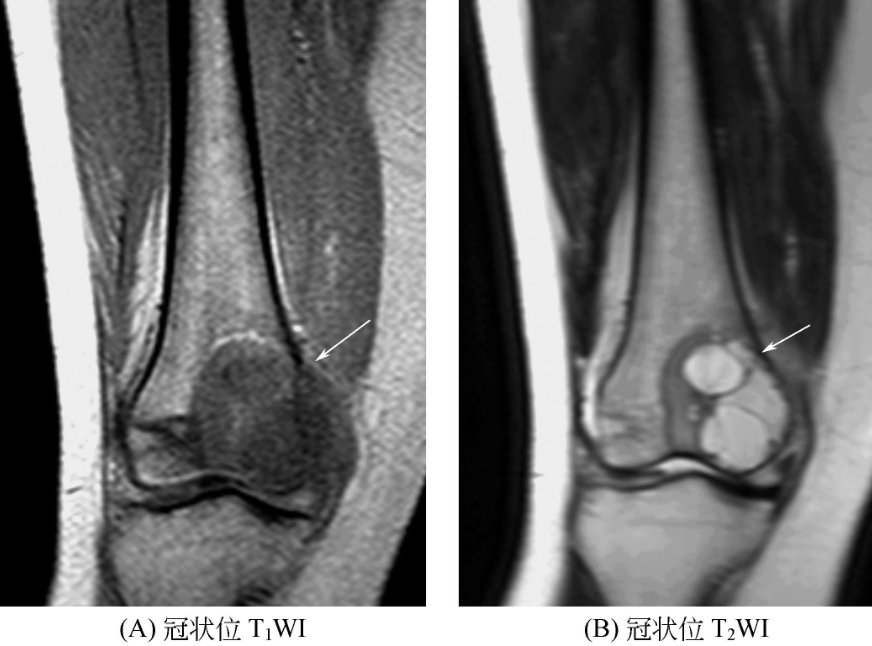

四、成软骨细胞瘤

骨骺或骨端圆形或不规则形病灶,少数呈分叶状或多房状。T1WI一般为欠均匀的等低信号;T2WI呈混杂信号,软骨基质呈较高信号,钙化、出血后形成的含铁血黄素呈低信号;病灶边缘常有低信号硬化环,周围可见斑片状骨髓水肿,病变可穿破骨皮质形成局限性软组织肿块。骨膜反应少见。邻近软组织可出现肿胀,可有关节积液(图4)。

图4 成软骨细胞瘤